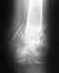

ЗДРАВСТВУЙТЕ!!!ПОДСКАЖИТЕ ПОЖАЛУЙСТА.3 года назад был перелом большеберцовой кости.Внутрь кости поставили длиный гвоздь и закрепили вверху и внизу по два шурупа.через полгода нижние шурупы удалили.Верхние и длинный оставили навсегда.Год после удаления проблем небыло.Но сейчас имею боль при ходбе в области перелома каждый день.Подскажите что делать???удалять остальные шурупи и гвоздь?поможет ли это???Большое спасибо

Выложите, пожалуйста свежие рентгенограммы!Голень на всем протяжении